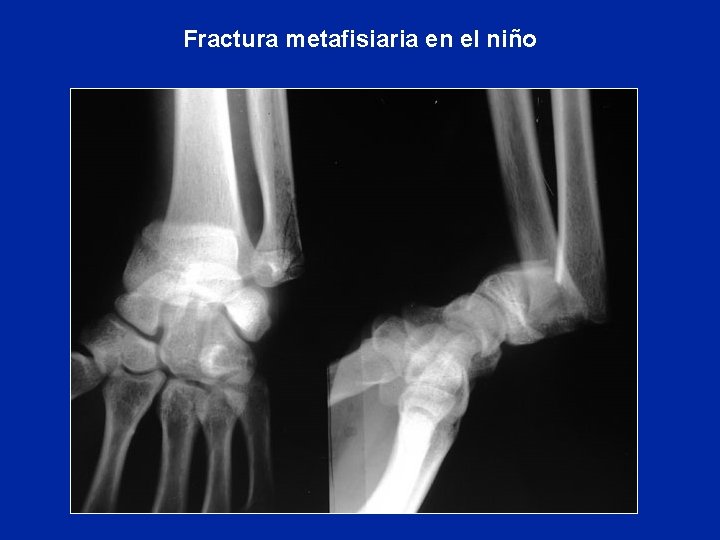

Fracturas del niño Fractura en tubo de plomo

Fractura metafisiaria en el niño

Fracturas del niño Salter-Harris 1 Salter-Harris 2 Salter-Harris 3 Salter-Harris 4 Desprendimientos epifisiarios